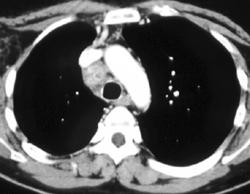

Extramedullary Hematopoesis